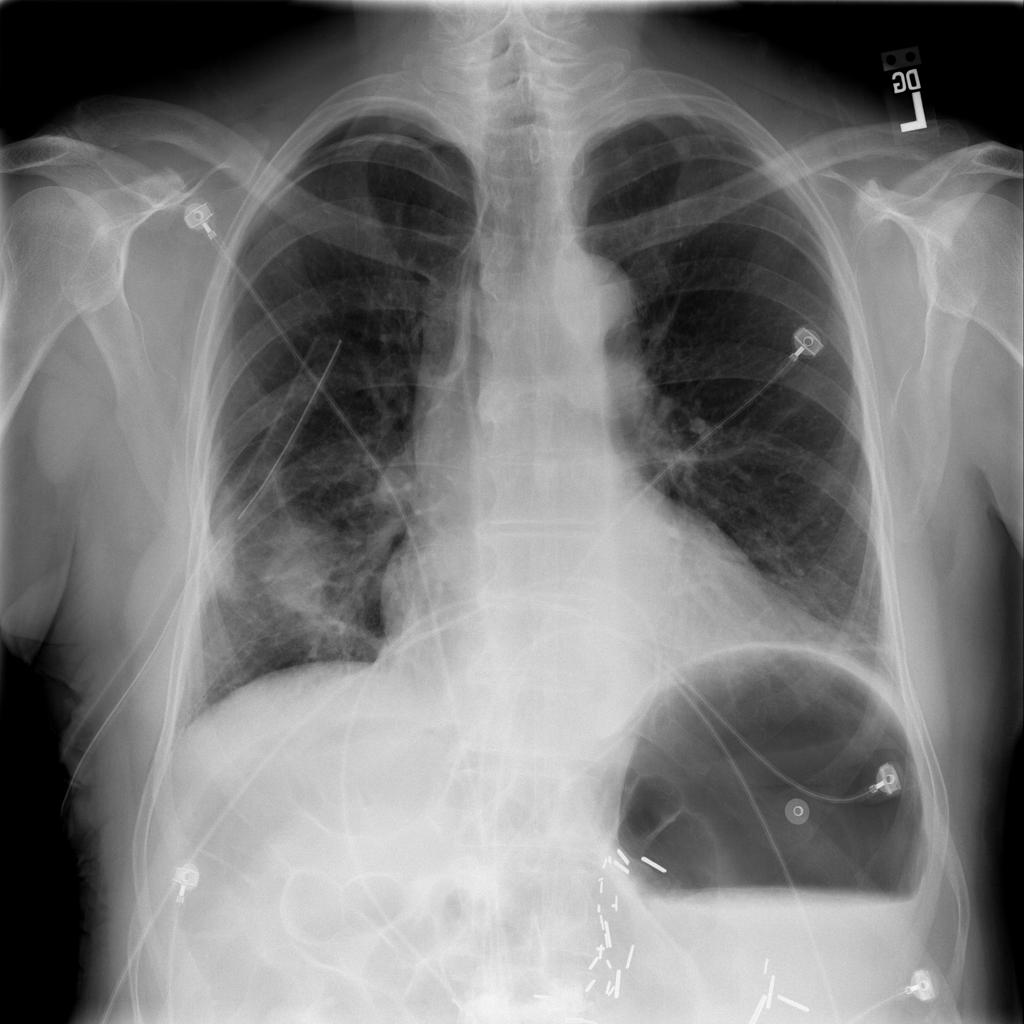

PAT-4639 · IMG-012Pneumothorax

PAT-4639 · IMG-012

AP